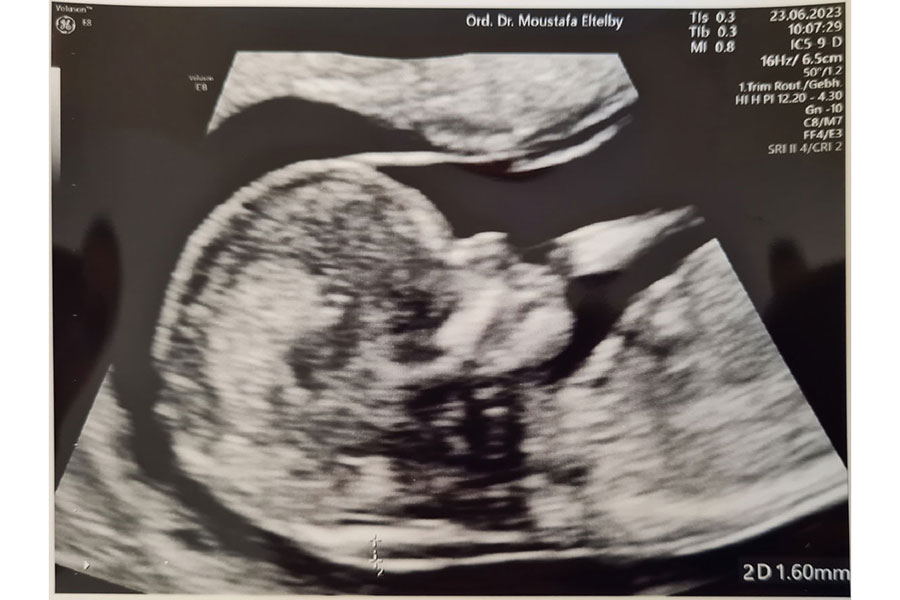

Gängige Methoden sind zum einen die nicht-invasiven, nur außerhalb des Körpers vorgenommenen Untersuchungen wie die Ultraschalluntersuchung (Sonographie), zu denen die Nackentransparenzmessung, die Nasenbeinmessung (in der 12. bis 14. Schwangerschaftswoche), die Fetometrie, der Feinultraschall, die Doppler-Sonographie, der 3D-Ultraschall und der 4D-Ultraschall gehören. Auch die Untersuchungen von Hormonkonzentrationen im mütterlichen Blut (serologische Untersuchungen) wie beispielsweise der Triple-Test, der Quadruple-Test und als Kombination beider Methoden das Erst-Trimester-Screening (ETS, eine Untersuchung im ersten Schwangerschaftsdrittel) und das integrierte Screening (kombinierte Untersuchung der biochemischen Serum-Parameter zur Risikoermittlung für fetale Chromosomen- und Verschlussstörungen) gehören zu den nicht-invasiven Methoden. Invasive, das heißt innerhalb des Körpers vorgenommene Untersuchungen der Pränataldiagnostik sind die Chorionzottenbiopsie (CVS), die Amniozentese (AC) und die Nabelschnurpunktion.